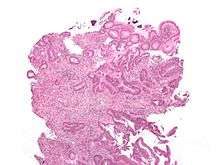

The microscopic cellular characteristics of the tumor are usually reported from the analysis of tissue taken from a biopsy or surgery. A pathology report usually contains a description of cell type and grade. The most common colon cancer cell type is adenocarcinoma (98% of cases).[54] Other, rarer types include lymphoma and squamous cell carcinoma.

Microscopy

Adenocarcinoma is a malignant epithelial tumor, originating from superficial glandular epithelial cells lining the colon and rectum. It invades the wall, infiltrating the muscularis mucosae layer, the submucosa, and then the muscularis propria. Tumor cells describe irregular tubular structures, harboring pluristratification, multiple lumens, reduced stroma ("back to back" aspect). Sometimes, tumor cells are discohesive and secrete mucus, which invades the interstitium producing large pools of mucus/colloid (optically "empty" spaces). This occurs in mucinous (colloid) adenocarcinoma, in which cells are poorly differentiated. If the mucus remains inside the tumor cell, it pushes the nucleus at the periphery. This occurs in "signet-ring cell." Depending on glandular architecture, cellular pleomorphism, and mucosecretion of the predominant pattern, adenocarcinoma may present three degrees of differentiation: well, moderately, and poorly differentiated.[55]

Cancer — Invasive adenocarcinoma (the most common type of colorectal cancer). The cancerous cells are seen in the center and at the bottom right of the image (blue). Near normal colon-lining cells are seen at the top right of the image.

Cancer — Invasive adenocarcinoma (the most common type of colorectal cancer). The cancerous cells are seen in the center and at the bottom right of the image (blue). Near normal colon-lining cells are seen at the top right of the image._Endoscopic_resection.jpg) Cancer — Histopathologic image of colonic carcinoid